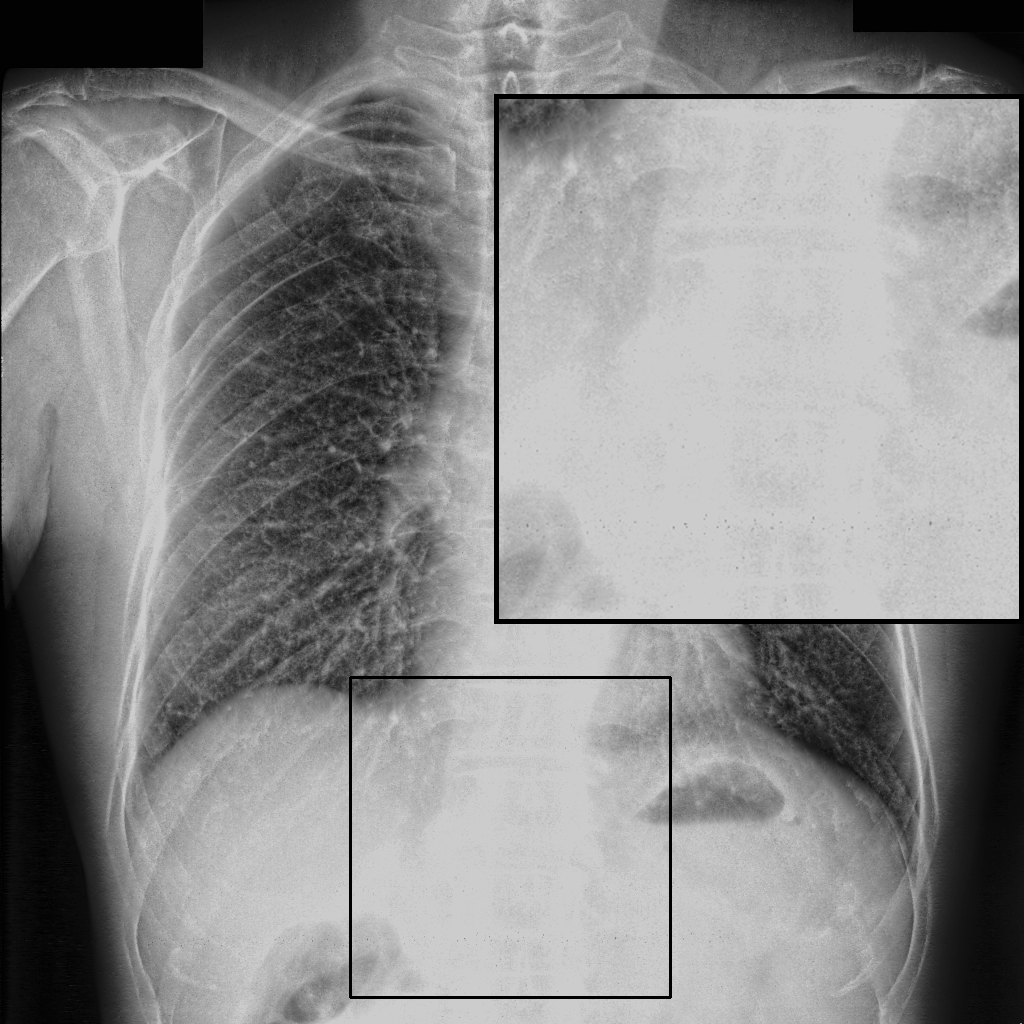

Figure 4: Visual examples of different image enhancement methods across datasets; first and second columns present results from the JSRT and Montgomery County Chest X-ray datasets, respectively, while third and fourth columns show results from the NIH Chest X-ray and CheXpert datasets

4.5 A Visual Assessment

Fig. 4 presents representative visual examples demonstrating the superiority of our method in enhancing vertebral contrast compared to several traditional and learning-based image enhancement techniques. The first and second columns show results from the JSRT and Montgomery County Chest X-ray datasets, while the third and fourth columns display results from the NIH ChestX-ray14 and CheXpert datasets. Across all datasets, the highlighted regions of interest (ROIs) emphasize the spinal areas, where fine structures and subtle details are critical for diagnostic assessment. Our method, XVertNet, consistently reveals clearer and more distinct spinal structures without introducing notable artifacts, preserving both global and local anatomical information. In contrast, traditional methods such as CLAHE [7] and Farbman et al. [19] often fail to enhance these subtle features effectively, either producing over-smoothed results or excessively sharpening noise. Similarly, learning-based methods such as ZSSR [43] and Madmad et al. [68] exhibit difficulties in generalizing across different datasets, leading to either insufficient enhancement or visible artifacts. Zero-DCE [33], although effective for natural images, struggles to adapt to the uniform and low-contrast nature of medical X-rays and was not able to supply clear enough contrast-enhanced vertebral structures.

These visual comparisons underline the clinical relevance of our approach. XVertNet successfully enhances diagnostically important structures, particularly in challenging anatomical regions like the spine, where competing methods either distort the features or fail to sufficiently reveal them. This highlights the value of integrating targeted enhancement strategies that are specifically tailored to the unique characteristics of medical imaging data.